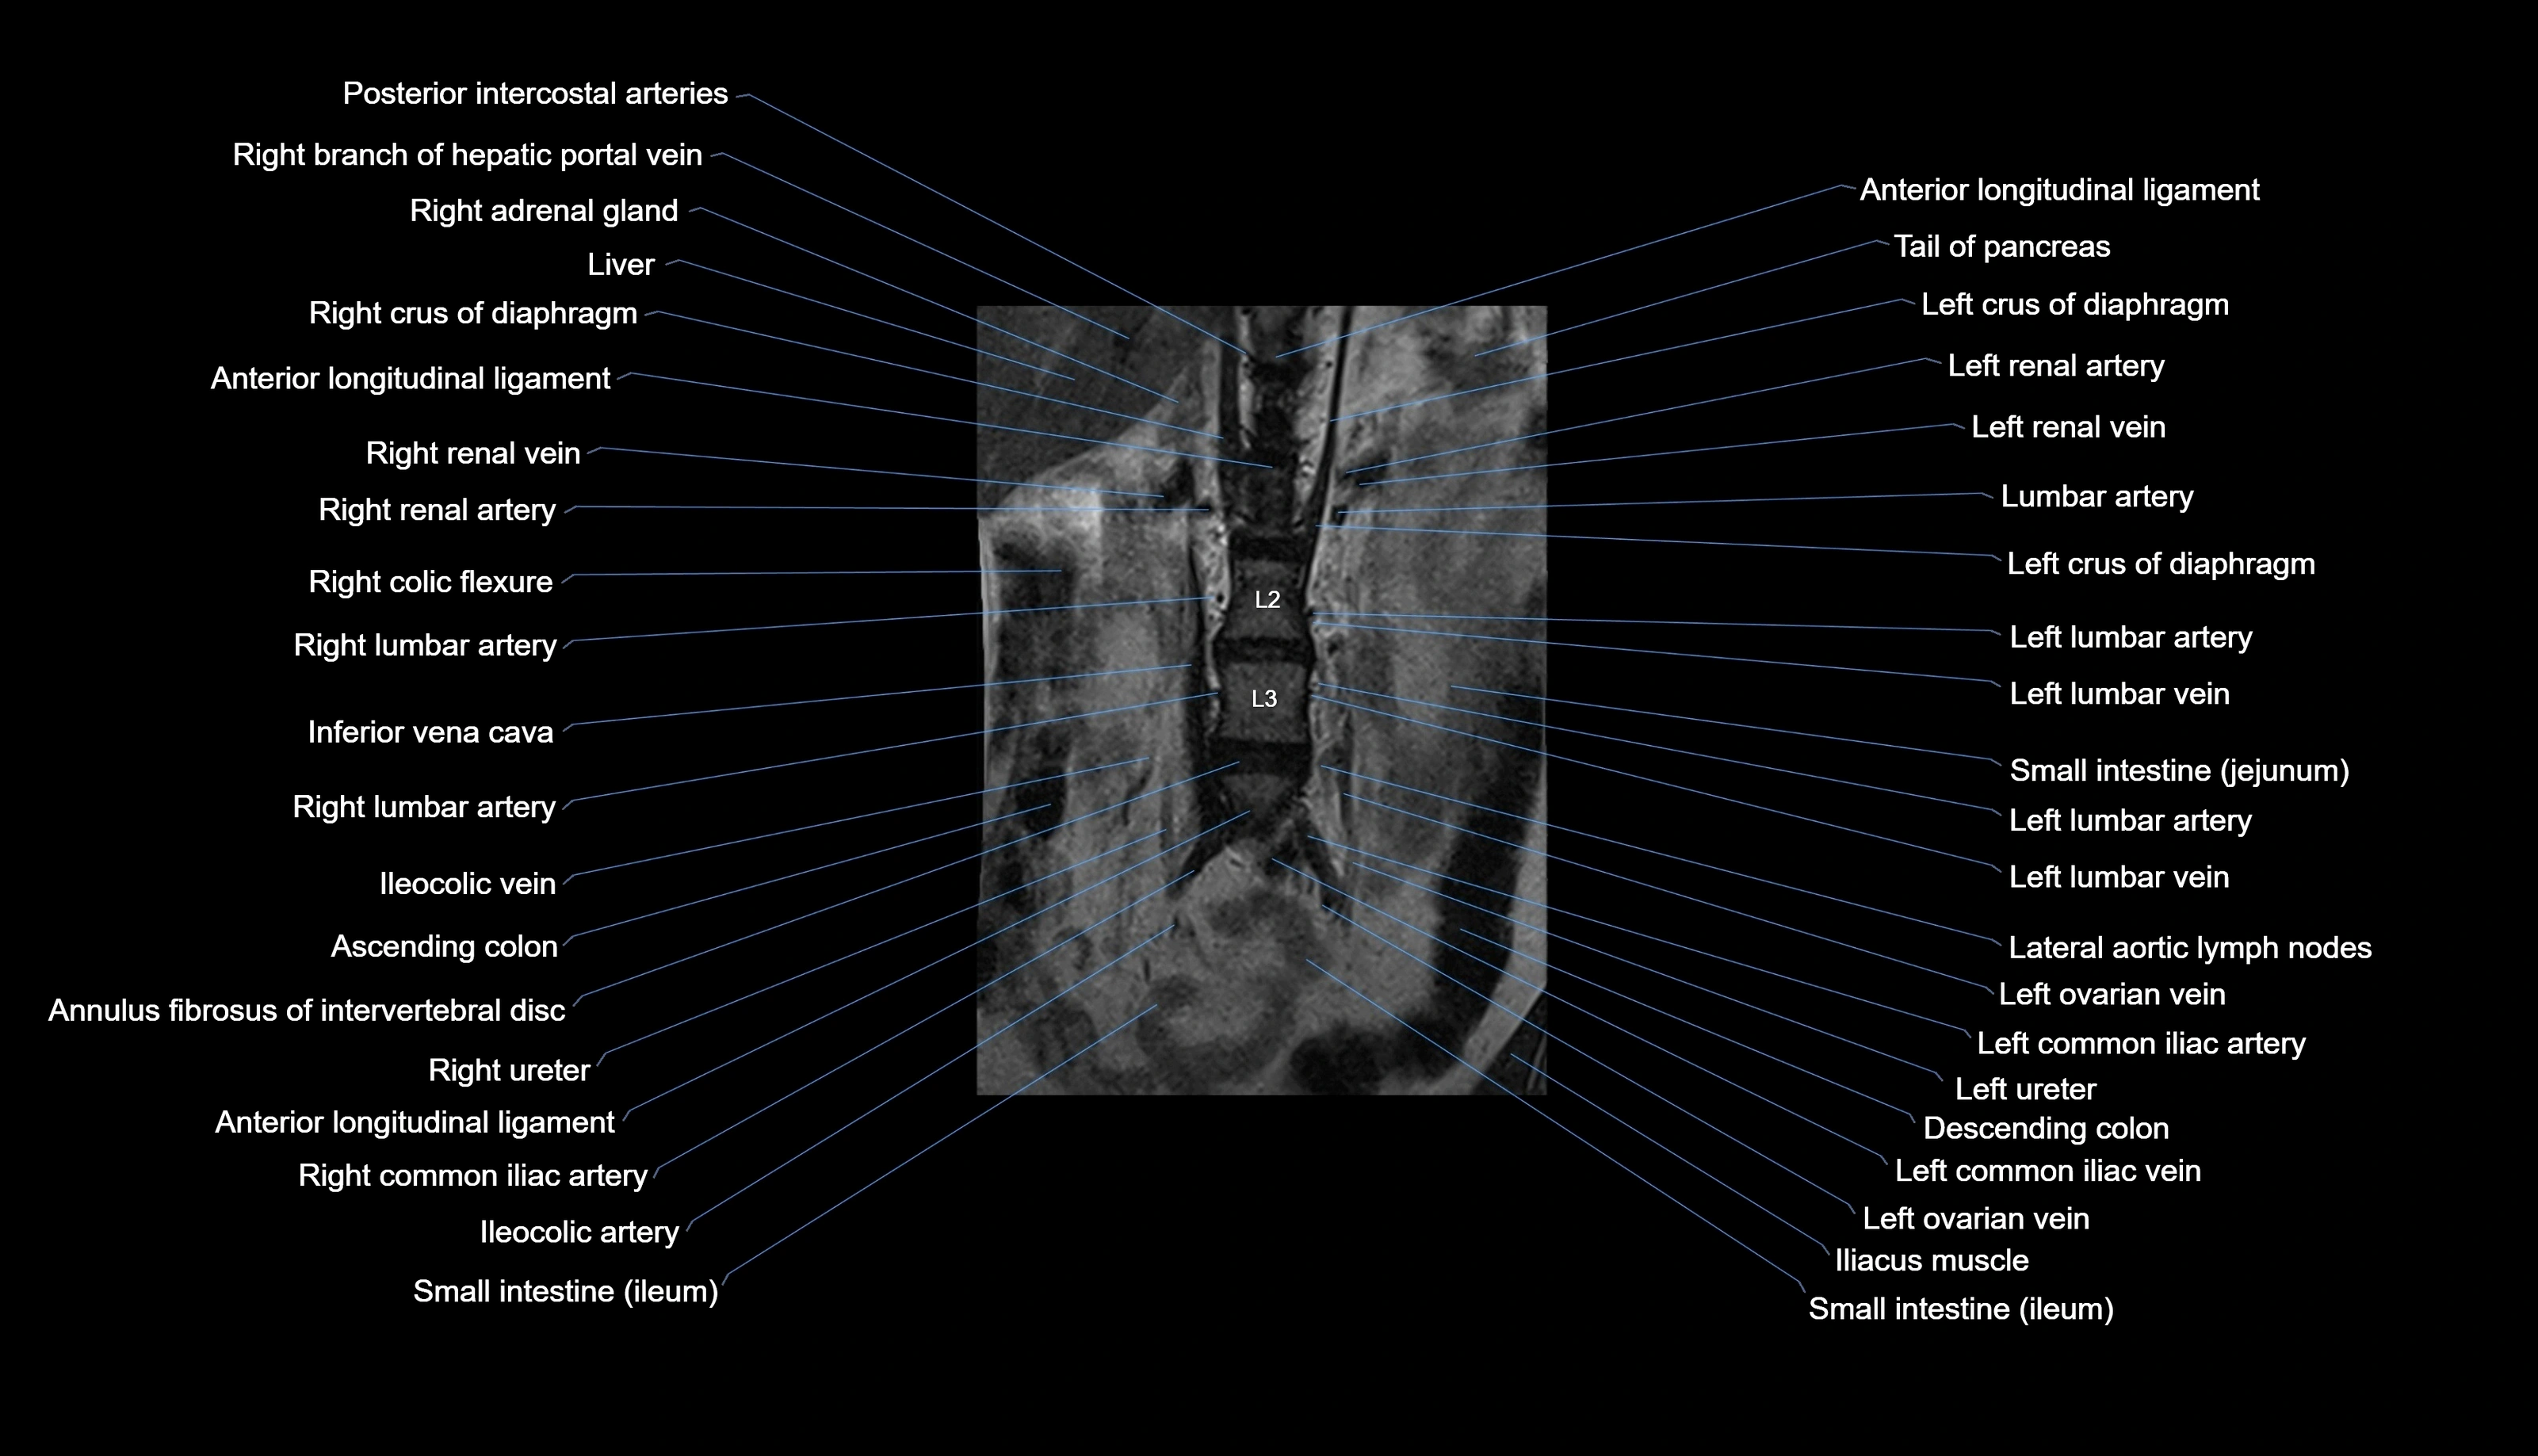

MRI images